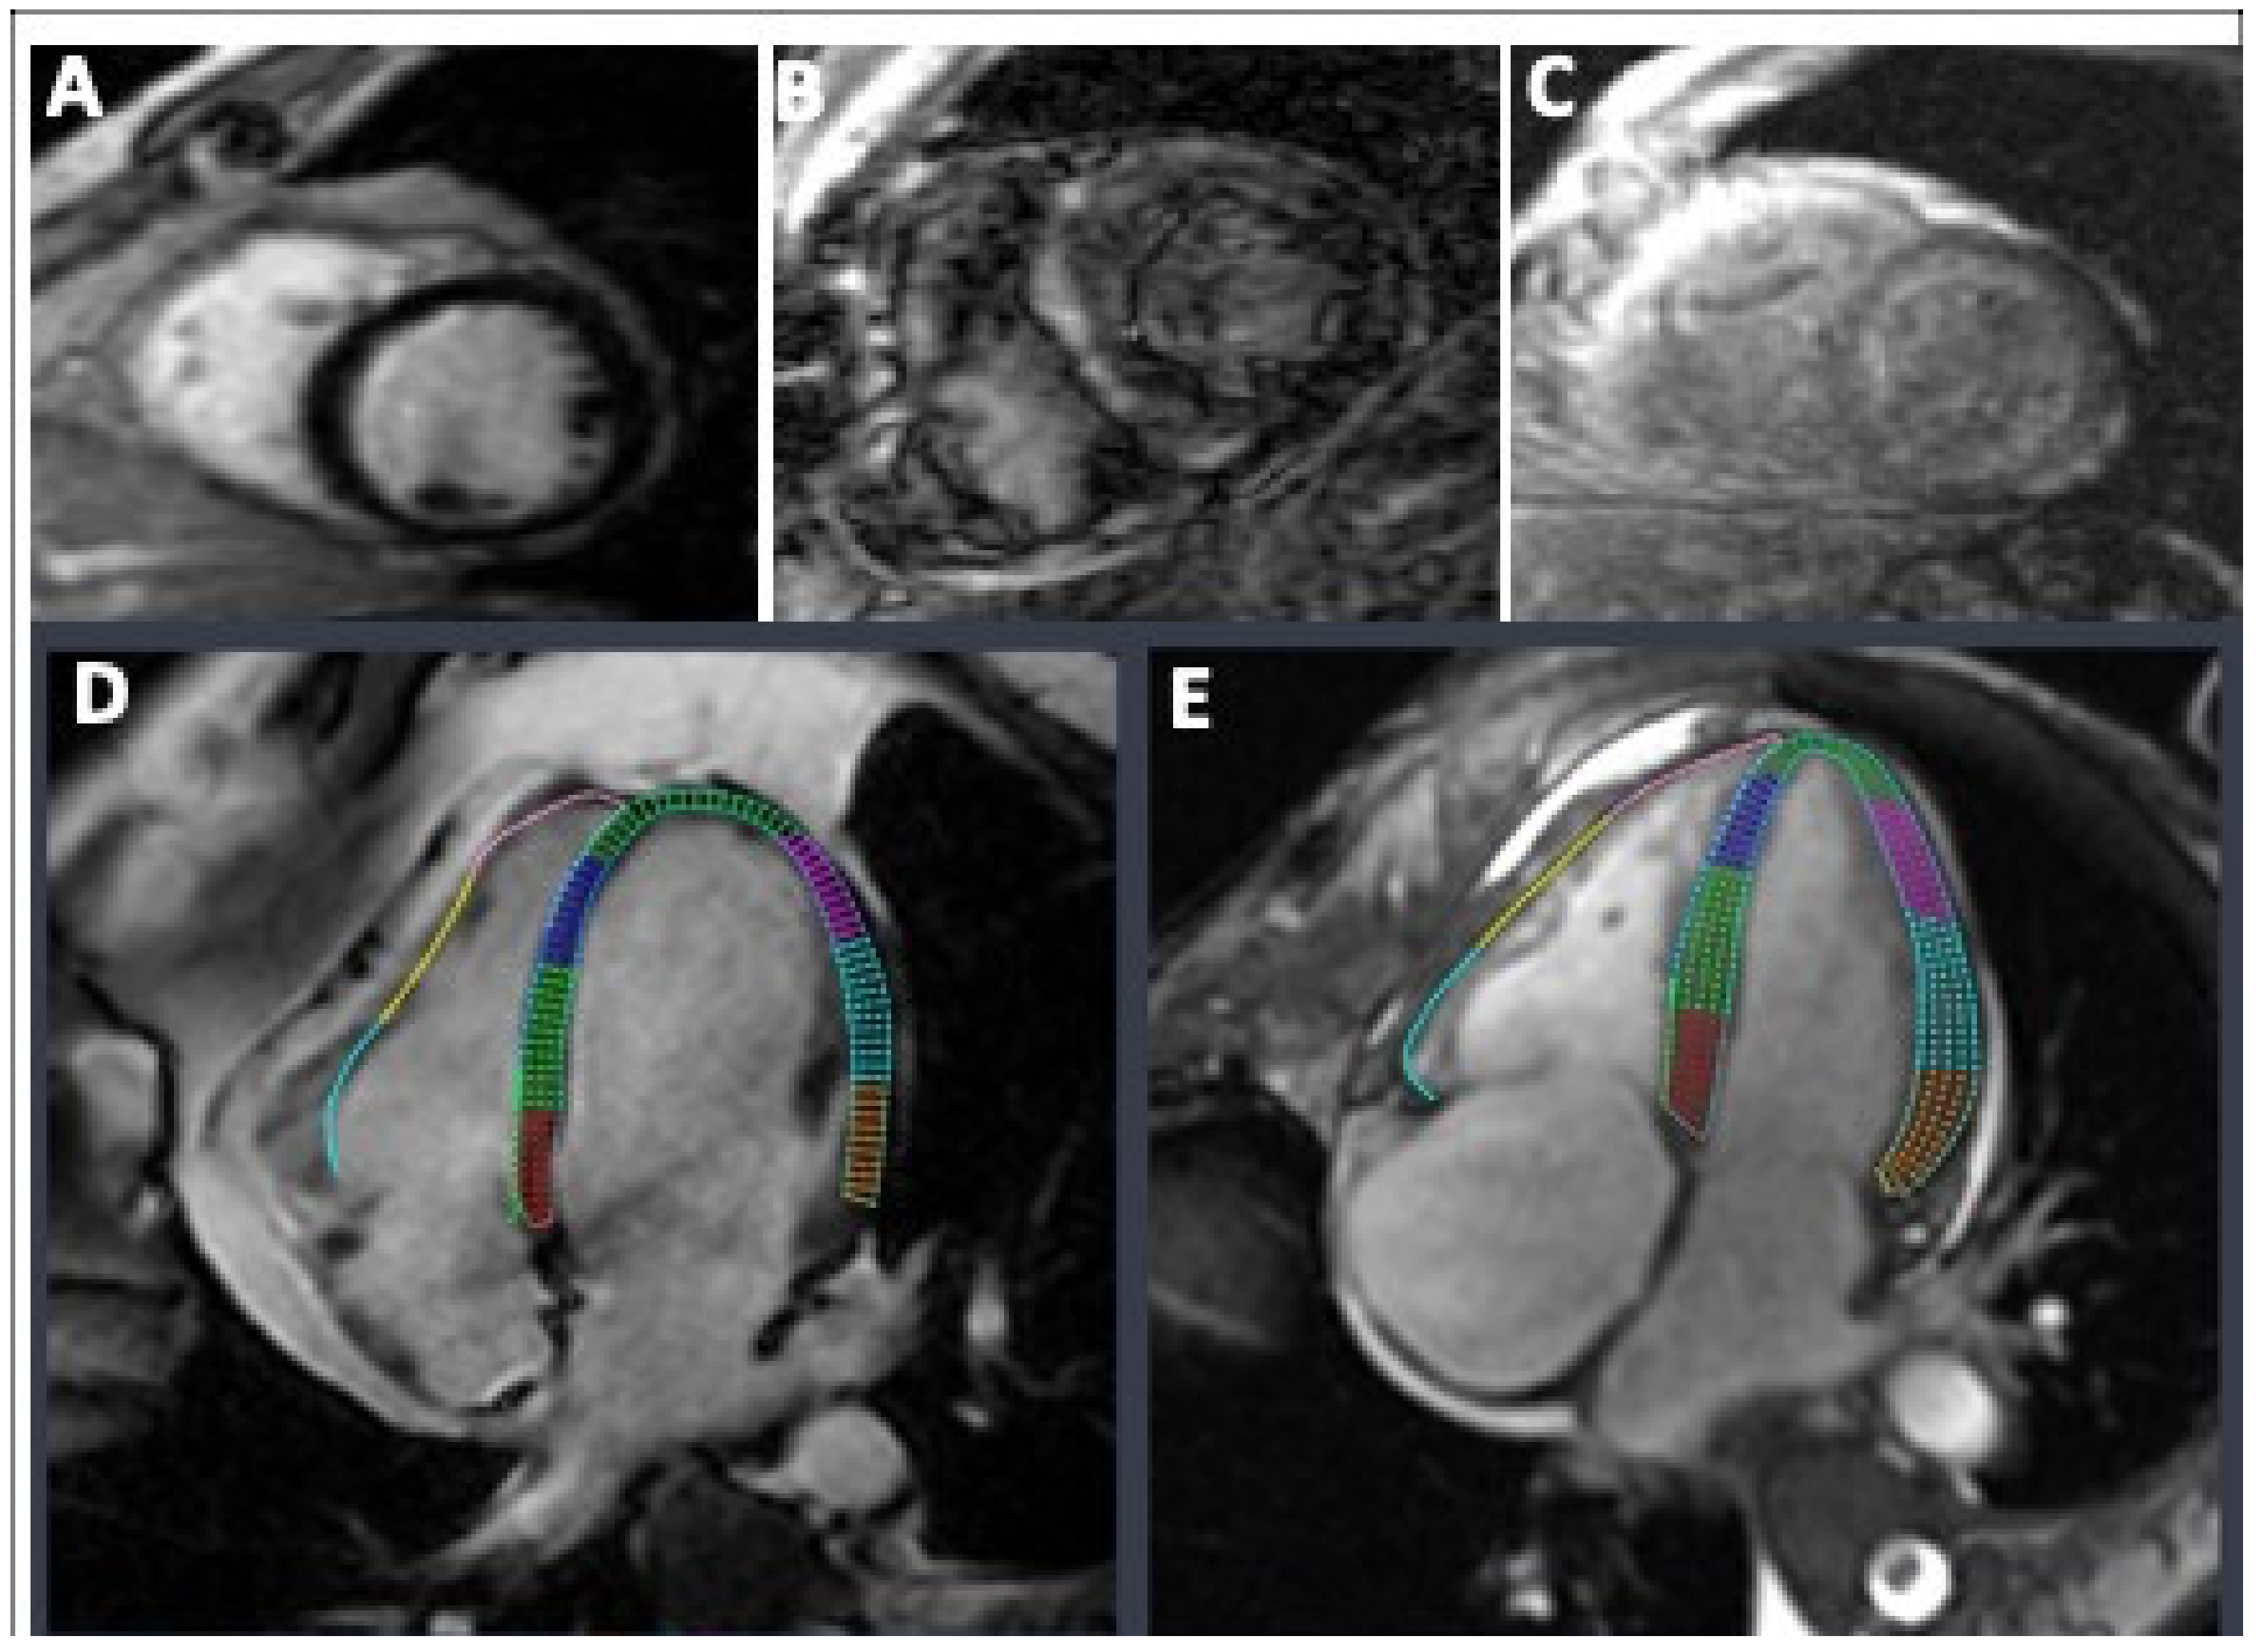

2.4. Strain Analysis

3.3. Cardiac MRI Assessment of Left Ventricular (LV) Deformation

3.3.1. LV Circumferential, Radial and Longitudinal Strains